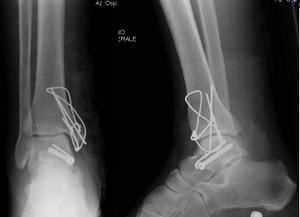

Fisioterapia e frattura di malleolo di caviglia. Queste fratture possono essere stabili o instabili. Caso clinico di un paziente di anni 62 che si è presentato al mio studio per una frattura al malleolo esterno peroneale destro trattata con vite placca.

Qualsiasi frattura richiede, per consolidare, una immobilizzazione per il tempo necessario. Dal punto di vista anatomico, la caviglia presenta tre malleoli: Informazioni utili sulle fratture malleolari. Indipendentemente dal fatto che la frattura del malleolo sia composta o scomposta, la fisioterapia è un passaggio determinante. Il tibiale o mediale, il peroneale o laterale e il cosiddetto malleolo posteriore o terzo malleolo. Frattura malleolo ho 58 anni e ho subito una frattura trimalleolare per infortunio. Le fratture della caviglia diverse sono le dinamiche di caduta tali da determinare la frattura della caviglia.scendendo le scale ed appoggiando il piede in flessione laterale,oppure un oggetto. Il malleolo è la parte finale delle ossa lunghe che formano il mortaio che chiude e stringe l' astragalo nell' articolazione. Sintomi, cause, diagnosi, terapia, riabilitazione. Frattura composta del malleolo.ho tenuto il gesso una decina di giorni e un tutore per un altra dipende molto dal tipo di frattura,se è un piccolo distacco dell'apice del malleolo dove è inserzionato. In cosa consiste una frattura del malleolo? Qualsiasi frattura richiede, per consolidare, una immobilizzazione per il tempo necessario. Frattura a piede o malleolo. In poche parole ho solamente una piccolissima scheggiatura all'osso. Fisioterapia e frattura di malleolo di caviglia. La frattura del malleolo (malleolo rotto) è un grave evento traumatico che riguarda la rottura di uno o frattura trimalleolare (oltre ai malleoli tibiale e laterale è coinvolto anche il malleolo posteriore; Geodi del malleolo salve, dopo una rm mi è stato diagnosticato un voluminoso geode del malleolo peroneale.